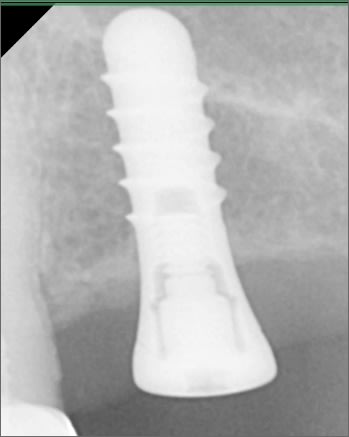

bonjour, pouvez vous m aider pour identifier cet implant?

Straumann RN pour moi.

+1